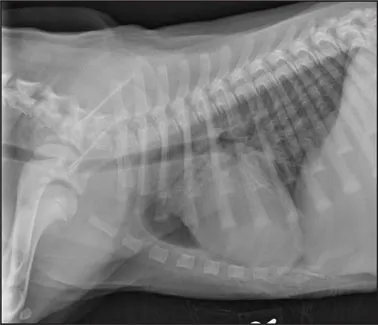

CASE 1.1 A 7-year-old neutered male Labrador Retriever who was hit by a car. You obtain these thoracic radiographs: Figs. 1.1a, b, left and right lateral projections, respectively; Figs. 1.1c, d, ventrodorsal and dorsoventral projections, respectively.

1.1a